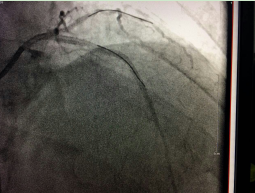

???我院成功開展市屬醫(yī)院首例冠狀動脈內(nèi)膜旋磨術???? 在心臟血管內(nèi)開“隧道”,用高速旋轉的鉆石磨頭將堵塞心臟血管的鈣化斑塊磨碎,以此打通血管進行冠心病的介入治療,這看起來像科幻電影里的場面,在我院實現(xiàn)。近日,我院完成了全市市屬醫(yī)院首例冠狀動脈內(nèi)膜旋磨手術,成功開通了血管,解除了患者長期存在的胸悶...